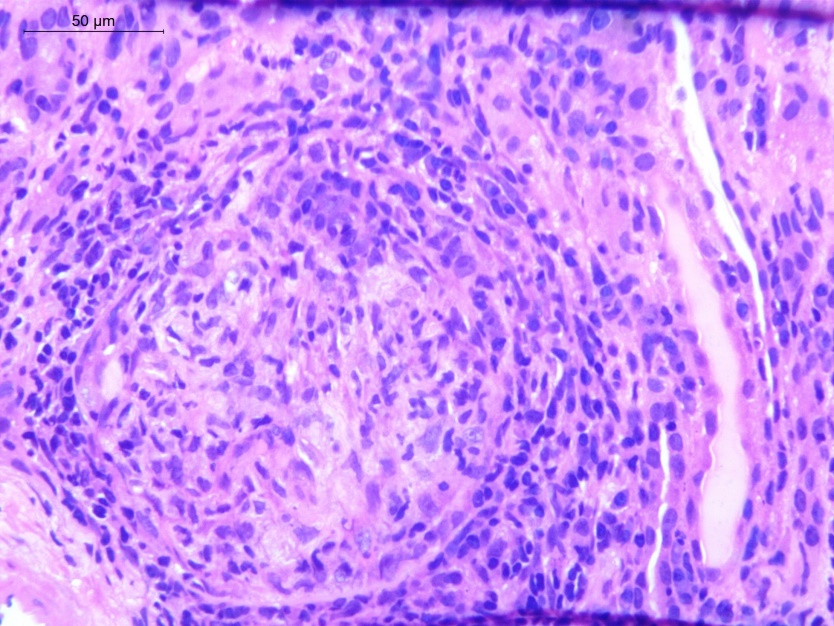

Figure 2 Glomerulus (PAS stain) showing cellular crescent (extracapillary proliferation) with ruptured Bowmans capsule (arrow) and periglomerular infilammatory infiltrate.

Anti-GBM disease of pregnancy is uncommon with its incidence being restricted to case reports. Crescent formation is the histopathologic hallmark of Anti-GBM disease with almost 95% of patients having evidence of crescent formation on kidney biopsy and in 80% of these patients more than 50% of glomeruli will be affected.10 The proportion of crescents has been observed to correlate strongly with the degree of renal impairment at presentation.